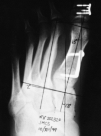

El estudio radiológico preoperatorio aportó un ángulo de hallux medio de 36° (22-46°), ángulo intermetatarsiano medio 16° (12-20°), ángulo cuneometatarsal medio 18° (12-23°), ángulo interfalángico medio 6° (0-13°); todos los sesamoideos se encontraban luxados o subluxados, y la fórmula metatarsal aportó nueve index plus minus y tres index minus. Ninguna de las articulaciones metatarsofalángicas era incongruente (Fig. 1).

Fig. 1.--Radiografía anteroposterior con estudio preoperatorio. Fig. 1.--Anteroposterior X-ray with pre-operative study.